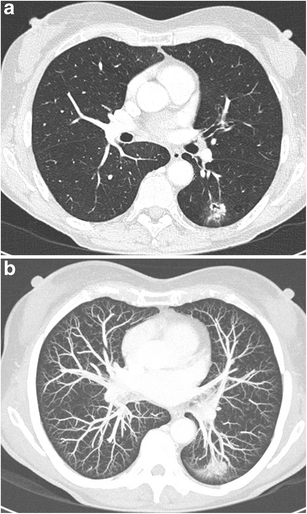

CT Thorax — Lung Window (B70f)

Axial CT slice through thorax with lung kernel (B70f), showing bilateral lung fields, airways, and pulmonary vasculature

CT Downloaded 2026-03-15

Ct

Lung Window 5.0 mm 120 kVp W:1500 L:-600

Wikimedia Commons: CT-Thorax-5.0-B70f-Lungs.jpg

CT Thorax — Lung Window (-700 HU)

Axial CT of thorax displayed at -700 HU window level, optimized for lung parenchyma evaluation

Lung Window 120 kVp W:1500 L:-700

Wikimedia Commons: CT Scan Thorax Lung -700 HU Window Level.jpg